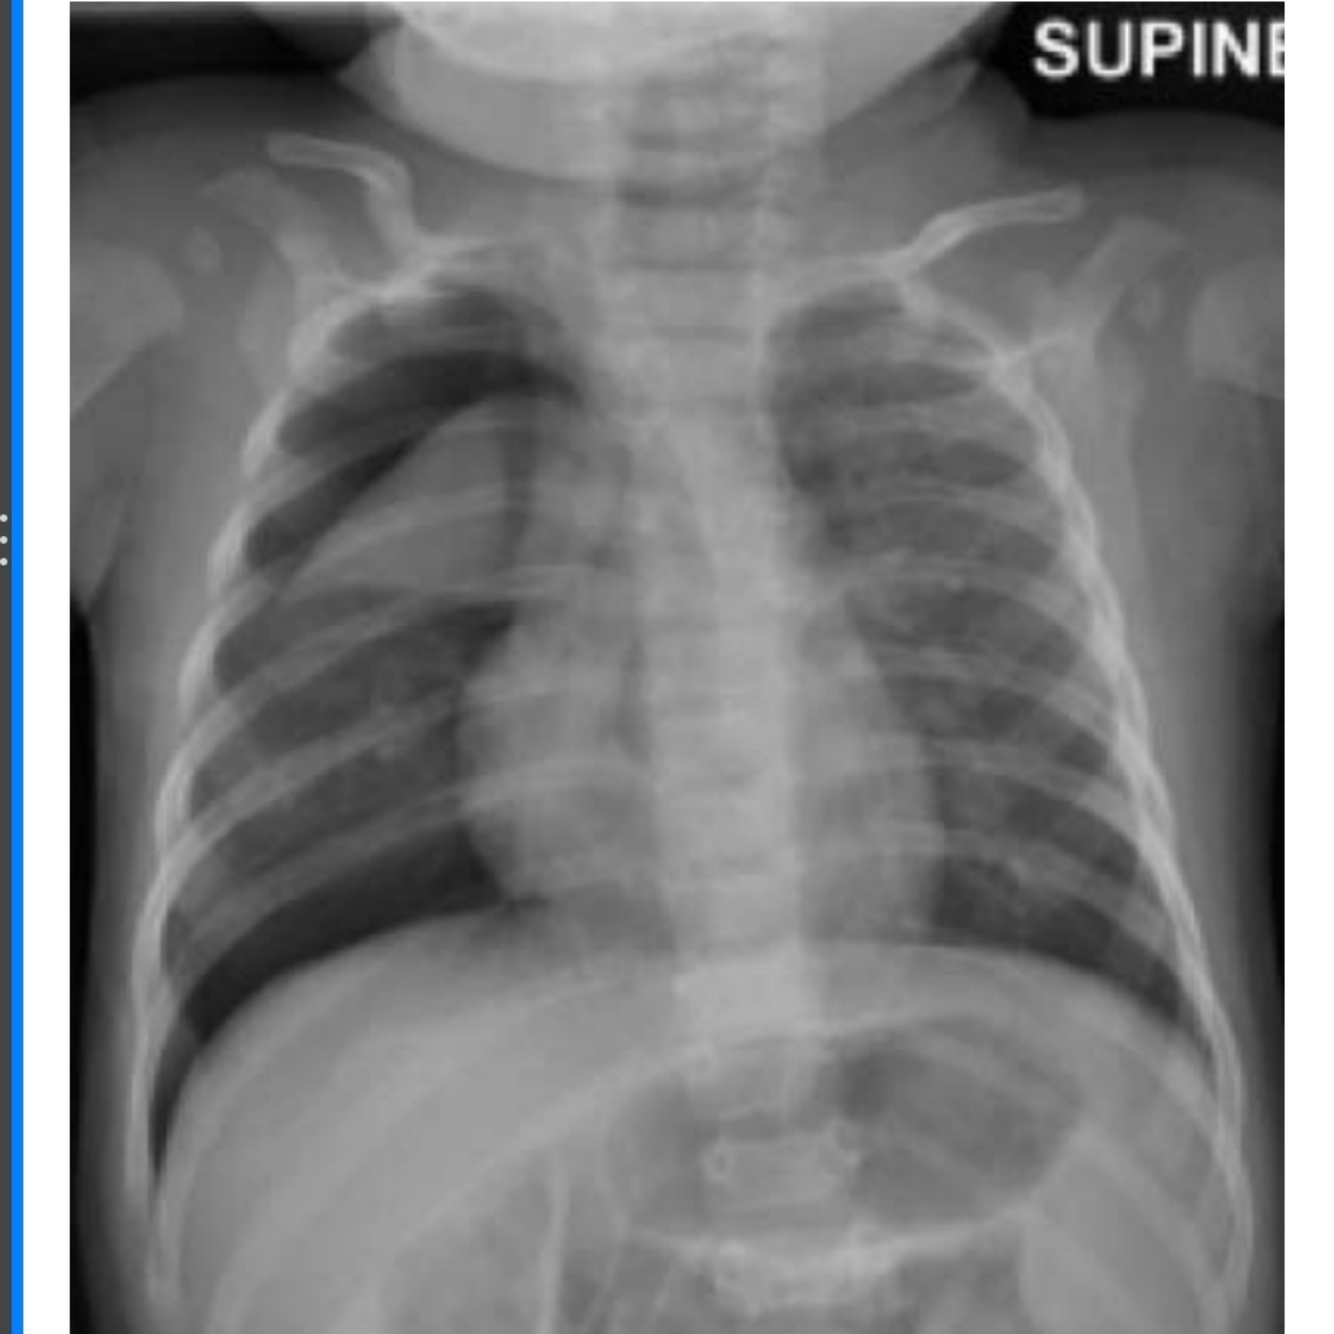

investigations Chest X-rays provided

explain the cXRs.

X-ray on inspiration

• Minimal hyperinflation seen on the left lung

• No foreign body (FB) seen

X-ray on expiration

• Hyperinflation of the left lung.

• In both inspiration and expiration images the diaphragms have not

moved.

• FB—not seen on the X-ray.